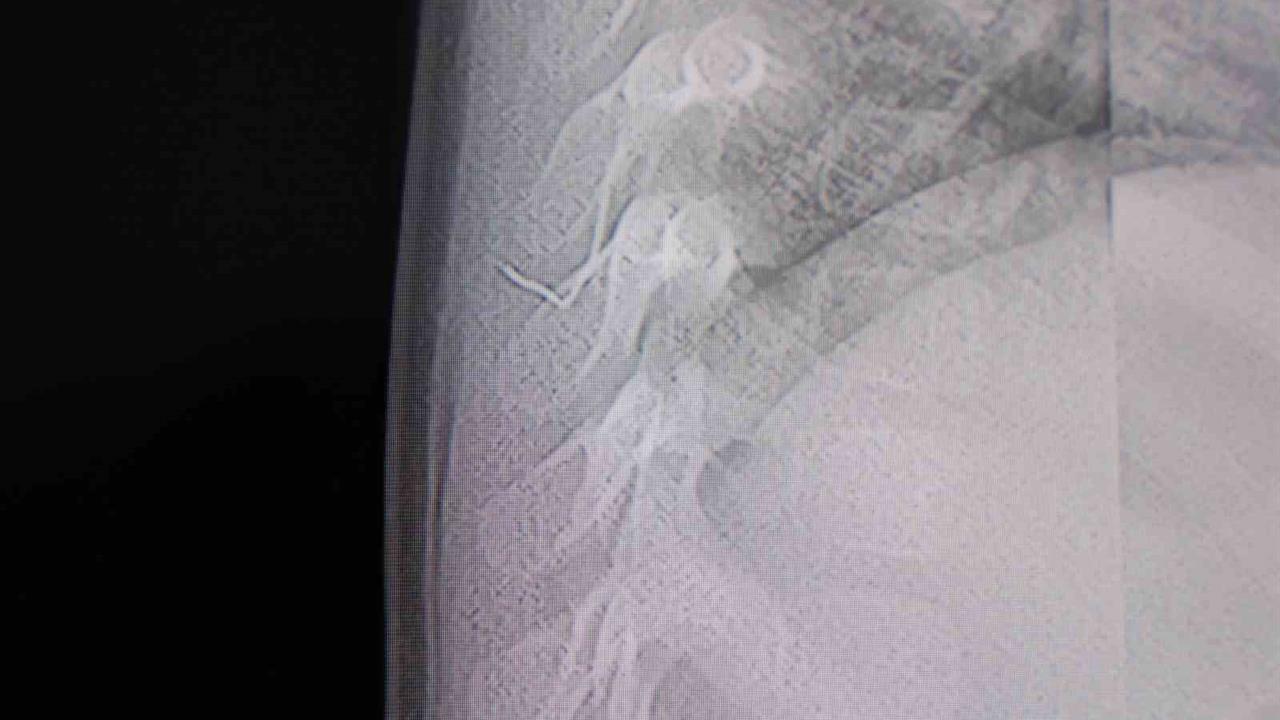

Kahramanmaraş'ta bir bebek, sırtında tespit edilen metal bir tel parçası ile hastaneye başvurdu. Konuyla ilgili açıklama yapan Prof. Dr. İdris Altun, "Bebeğin sırtında yabancı bir cisim olduğu söylenmişti. Ancak çıkarılamayacağı ve 8 yaşına kadar beklenmesi gerektiği ifade edilmişti. Bize başvurduğunda yapılan tetkiklerde, cilt altında, omurilik kanalına çok yakın ve akciğer zarına doğru ilerleyen bir yabancı cisim tespit ettik. Hastamızı tamamen uyutmadan, lokal anestezi ve sedasyon eşliğinde müdahale ederek lezyonu tamamen çıkardık" dedi.

Çıkarılan cismin, ince zımba teline benzer ve yaklaşık 2 santimetre uzunluğunda bir metal tel olduğu belirtildi. Prof. Dr. Altun, bu yabancı cismin alınmaması durumunda bölgede enfeksiyon gelişebileceğini ve enfeksiyonun omurilik kanalında ciddi hasarlara yol açabileceğini vurguladı. Ayrıca tel parçasının hareket etmesi durumunda omurilikte zedelenmelere neden olabileceği ve akciğer zarına batma riski taşıdığına dikkat çekti. Böyle bir durumda enfeksiyon ve ilerleyen süreçte tümörle karışabilecek sorunların ortaya çıkabileceği ifade edildi.